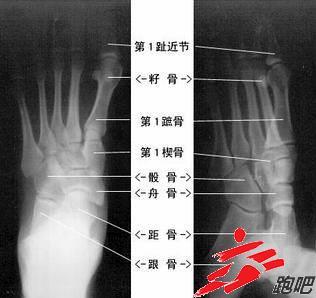

脚骨图解结构图片大全,正常脚骨的照片

足部骨骼图解大全

脚骨图片 结构图

脚骨结构图

脚骨图片解析

人体脚的骨骼结构图

脚骨图解结构

脚骨图解

脚骨名称示意图